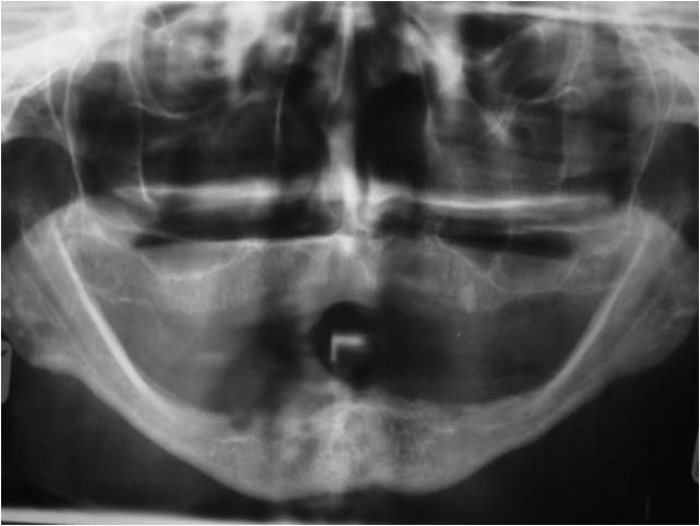

Raio X inicial